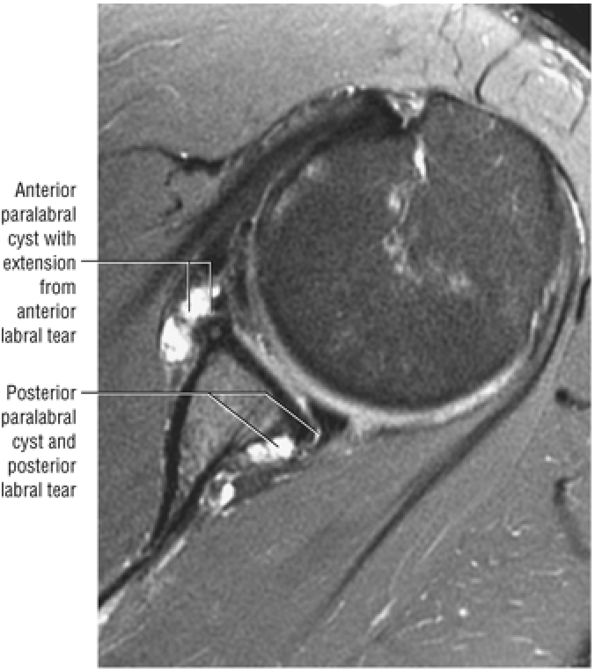

A separate FS PD-weighted FSE sequence is used to increase sensitivity to fluid and to identify paralabral cysts, articular cartilage labral avulsions, and muscle edema (Fig. 8.4). FSE sequences are less sensitive to intralabral signal intensity in the spectrum of degenerations or tears unless there is imbibed fluid. FSE (FS PD FSE) images, however, are superior for the demonstration of labral morphology in cases of avulsions or contour abnormalities.